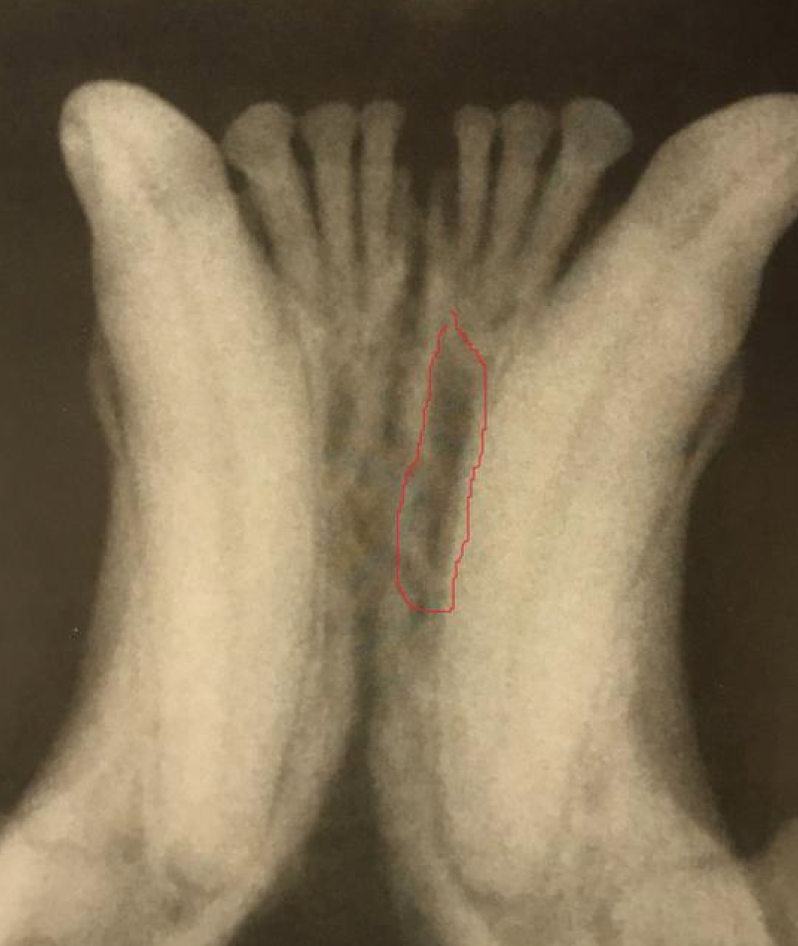

The lucency outlined in red is: